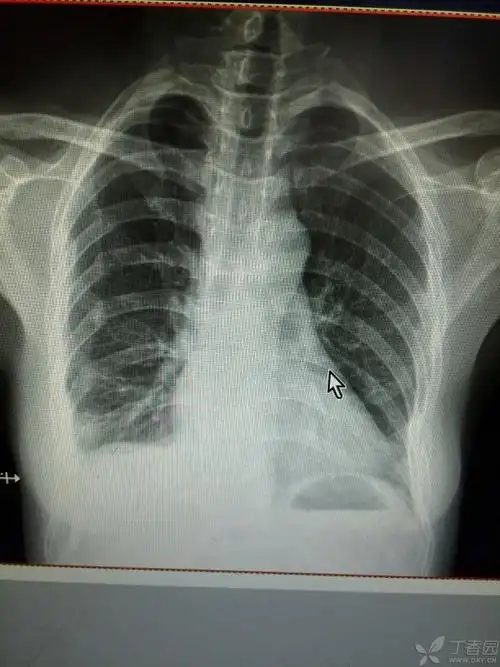

拍片显示三根肋骨骨折

胸部外伤,肋骨骨折,大家看是第几根?

病例24肋骨骨折

多发性肋骨骨折